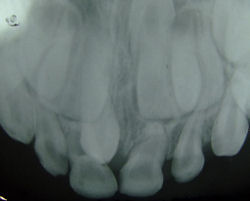

This slide is a cross section of a decalcified tooth.

Identify microscopically:

1. Pulp Chamber

2. Dentine

3. Cementum

4. Periodontium

5. Alveolar bone

Cross section of a decalcified tooth

Very low magnification

Very low magnification cross section of a decalcified tooth